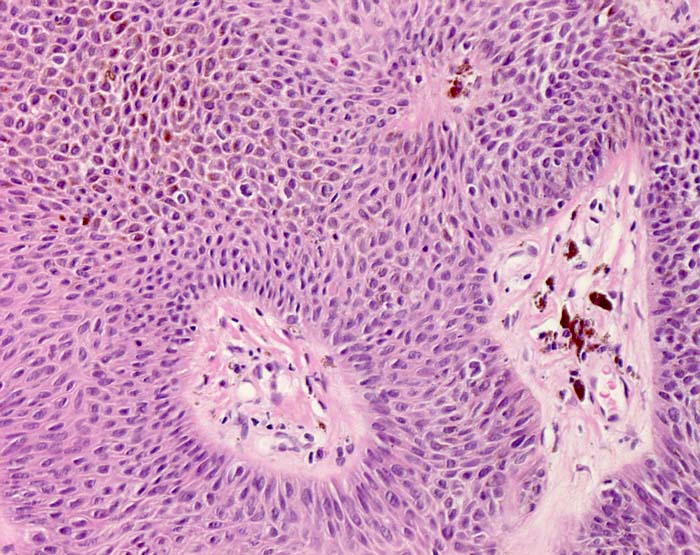

Histologie: Die grosse makroskopische Vielgestaltigkeit widerspiegelt sich auch in einer variablen Histologie. Unterschieden werden mehrere histologische Subtypen der seborrhoischen Keratose: Hyperkeratotischer Typ ( 3435), akanthotischer Typ (Kurspräparat), klonaler Typ ( 7284)( 7285), irritierte seborrhoische Keratose ( 3353)( 3356). Typisch für seborrhoische Keratosen sind umschriebene Wirbelbildungen von Tumorzellen, sogenannte squamous eddies ( 8065). Der retikuläre Typ ( 7838) entwickelt sich in chronisch UV exponierter Haut meist im Gesicht und geht oftmals hervor aus einer solaren Lentigo ( 7839).